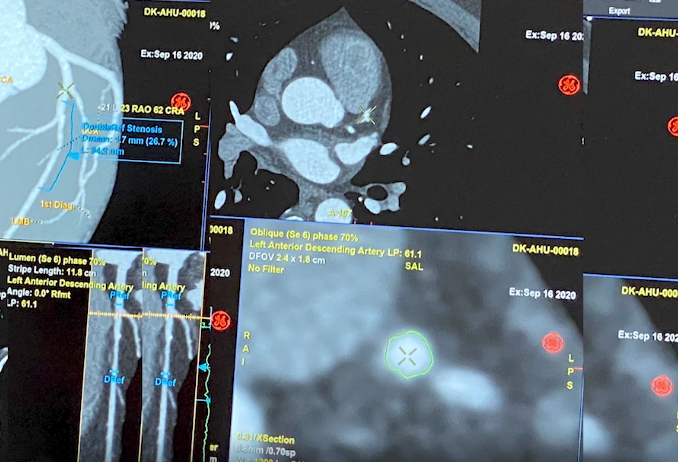

科莱特介绍,如今,基于人工智能的软件工具以及新兴的斑块表征算法,能在患者进入导管室前生成详细的血管造影路线图和虚拟生理模型。他强调,目前该领域正朝着在导管插入术前进行冠状动脉CTA的方向发展,以获取解剖和生理数据,从而制定个性化的治疗策略。

“人工智能驱动的CT软件和硬件组件都取得了进步,使得图像更加清晰,对斑块分析和生理方面的评估也更加准确,”科莱特说,“现在我们可以利用人工智能,了解狭窄背后的原因,例如是否存在脂质核心斑块、是否存在钙化等。”

科莱特还指出,CCTA不仅能提供功能和解剖数据,还能根据斑块成分进行风险分层。此外,CCTA是冠状动脉疾病纵向管理模式转变的基础,医生可以长期监测斑块的消退或进展,评估药物治疗效果。在导管室中,CCTA也将发挥越来越重要的作用,帮助更好地处理严重钙化病变。